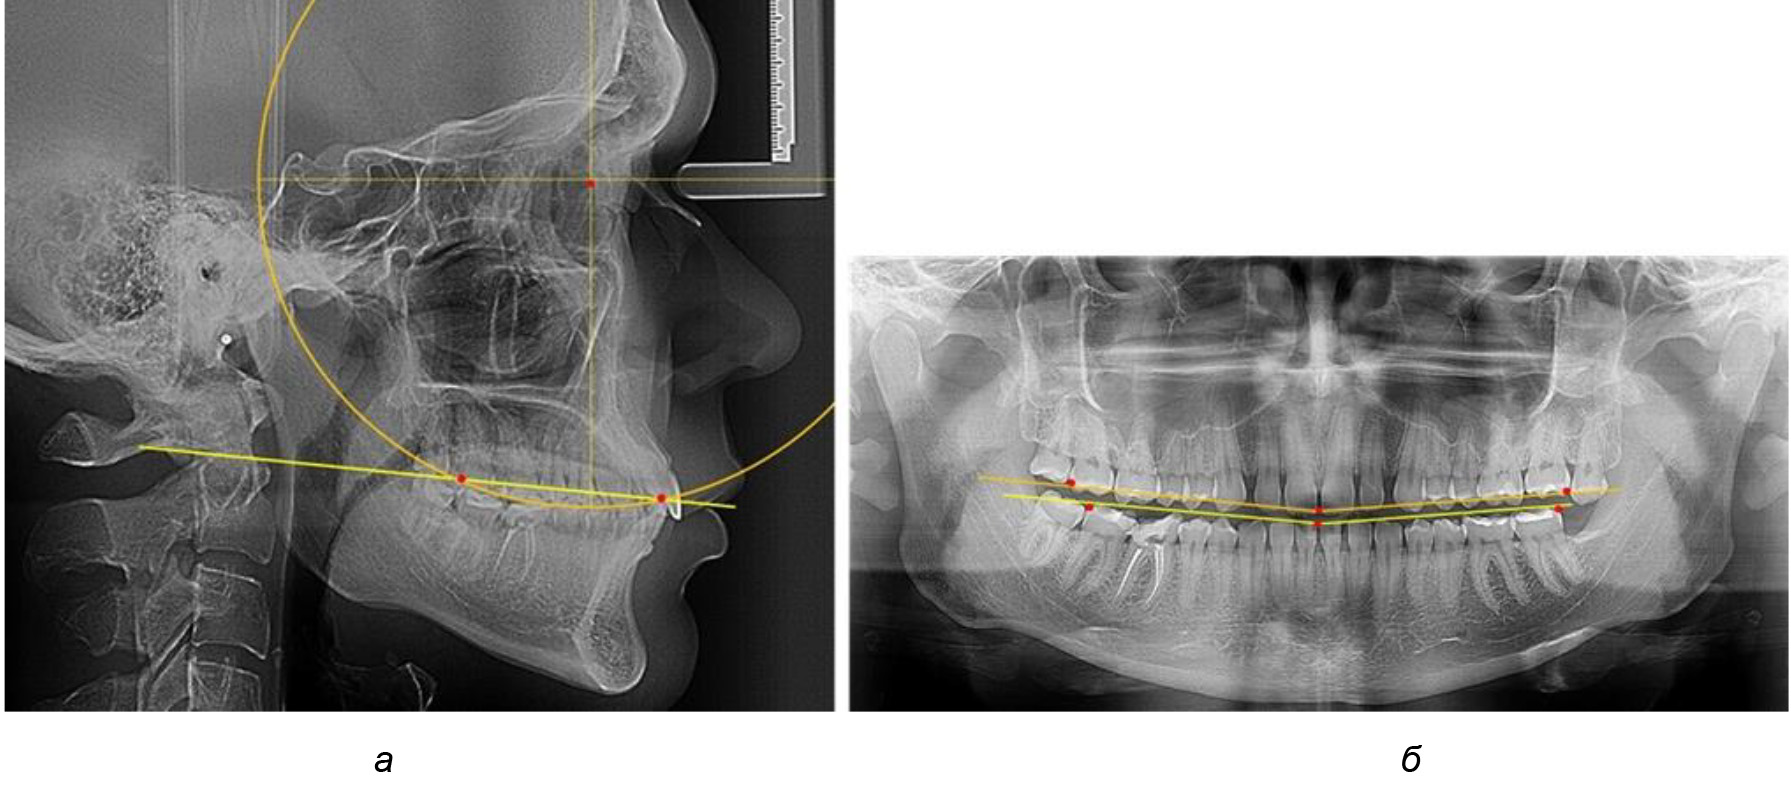

При анализе латеральных ТРГ устанавливали реперный окклюзионные точки в переднем и боковом отделе. Передняя точка устанавливалась на режущем крае нижнего медиального резца, которую в клинике ортодонтии обозначают как vPOcP. Дистальная точка второго нижнего моляра обозначалась как hPOcP. Измеряли расстояние между окклюзионными точками, что определяло сагиттальный размер окклюзионной линии. Использование программ PowerPoint позволило проводить окружность, проходящую по линии смыкания зубов через окклюзионные точки. Измеряли радиус окружности. Учитывая вариабельность размеров окклюзионной линии и радиуса окружности, определяли относительный показатель через отношение радиуса круга к длине сагиттального размера окклюзионной линии. Глубину окклюзионной кривой измеряли от точки наибольшей выпуклости до окклюзионной линии (рис. 1). На ортопантомограмме (ОПТГ) также соединяли окклюзионные точки правой и левой стороны и измеряли глубину окклюзионной кривой от точки наибольшей выпуклости до окклюзионной прямой линии. Результаты глубины кривой Spee сравнивали по данным ТРГ и ОПТГ.

Рис. 1. Метод определения кривой Spee на ТРГ (а) и на ОПТГ (б)

В 3-ю подгруппу вошли ТРГ и ОПТГ 14 человек 1-й группы, что составило (22,58 ± 5,31) % от общего количества людей 1-й группы. Величина угла нижней челюсти в среднем составила (114,85 ± 2,87)° и характеризовала горизонтальный тип нижней челюсти.

Глубина кривой Spee в среднем по 2-й подгруппе составил (2,94 ± 0,47) мм, что было меньше, чем в других подгруппах. Деление величины радиуса круга к длине окклюзионной линии составило 1,616 ± 0,02 (рис. 4).

Рис. 4. Особенности кривой Spee на ТРГ (а) и ОПТГ (б) у людей с горизонтальным типом лица